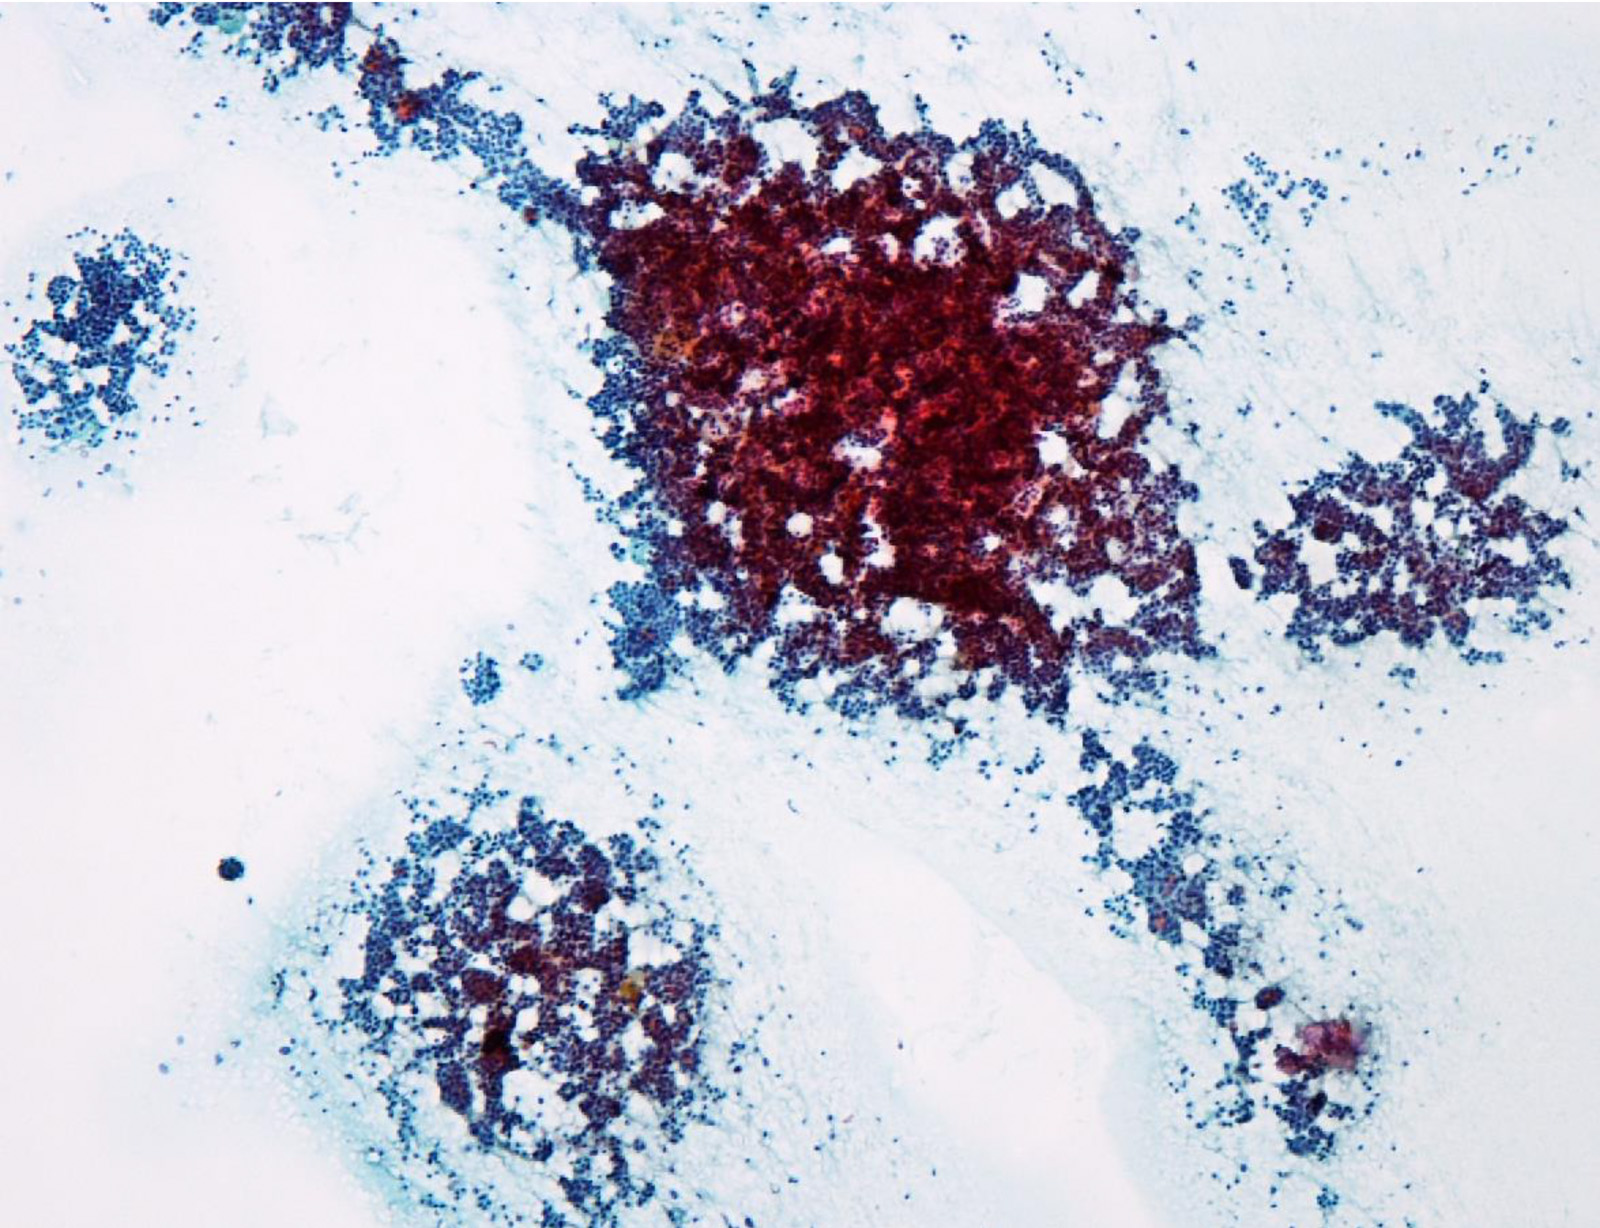

Cytology description

- Hypercellularity

- Small, round and dense colloid (hyaline colloid) may be present, sometimes within follicles

- Cells arranged in microfollicles or trabecular pattern

- Nuclear enlargement but may lack prominent nuclear features of papillary carcinoma (Am J Clin Pathol 1999;111:216)

- Highly suggestive of syncytial clusters, microfollicular architecture, chromatin clearing and nuclear grooves (Acta Cytol 2006;50:663)

- Classified by Bethesda system as categories III to VI

- Cytologically unable to distinguish between noninvasive and invasive

Cytology images

Contributed by Ayana Suzuki, C. T.